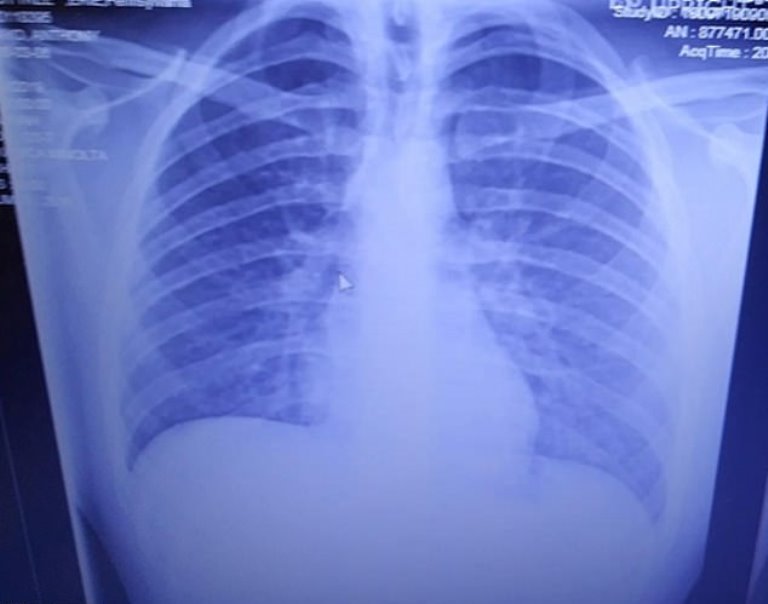

Chest Imaging Reveals Traits of VapingRelated Lung Injuries in Teens Lungs Filled With Vape This article examines what lung damage vaping can cause, whether secondhand vaping is safer, when to contact a doctor, and frequently asked questions about vaping. In august 2019, the cdc began tracking cases of severe lung problems in people who vape. During a vape session, you take an aerosol of chemicals and nicotine into your lungs. Recent research found that. Lungs Filled With Vape.

Lungs with vaping damage, baseline CT Stock Image C050/4442 Lungs Filled With Vape Thousands had lung damage that needed treatment in hospitals,. In august 2019, the cdc began tracking cases of severe lung problems in people who vape. Recent research found that vaping may cause scarring of lung tissue, or constrictive bronchiolitis. During a vape session, you take an aerosol of chemicals and nicotine into your lungs. You may have seen news reports. Lungs Filled With Vape.